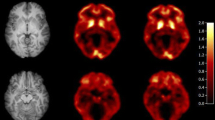

Test-retest data belonging to twelve participants, who underwent two 90 min [11C]PiB PET scans, were retrospectively included. The voxel-based implementation of the two-step simplified reference tissue model with cerebellar grey matter as reference tissue was used to compute R1 images. Next, test-retest variability was calculated, and test and retest R1 measures were compared using linear mixed effect models and a Bland-Altman analysis.

The PPET software tool [14] with the voxel-based implementation of the two-step simplified reference tissue model (SRTM2), as validated for [11C]PiB, and cerebellar grey matter as reference tissue were used to compute relative tracer delivery (R1) images [15,16,17]. For SRTM2, k2' was determined across all voxels with a BPND higher than 0.05 by taking the median k2' from a first run using receptor parametric mapping (RPM) [18]. Regional R1 values were obtained by superimposing the following grey matter VOIs on the parametric images: medial and lateral anterior temporal lobe, posterior temporal lobe, superior, middle and inferior temporal gyrus, fusiform gyrus, parahippocampal and ambient gyrus, anterior and posterior cingulate gyrus, middle and orbitofrontal gyrus, gyrus rectus, inferior and superior frontal gyrus, pre- and post-central gyrus, superior parietal gyrus and the (infero)lateral remainder of the parietal lobe and a global cortical composite region (i.e. volume-weighted average across all target regions).

LME analyses showed that test and retest R1 values were strongly correlated and that the slope was not significantly different from 1 (R2=0.92, slope=0.98 C.I. [0.94–1.01], p<0.001). Furthermore, amyloid status as measured by visual read did not have a significant effect on this relationship. Finally, Bland-Altman analysis showed a negligible bias (0.69±3.07 %) between test and retest R1 (Fig. 1). All analyses were also carried out using RPM-derived R1 which resulted in essentially identical results (data not shown).